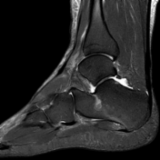

A patient presents with pain in the sole of the foot on both sides, especially on the left side, which occurs with exertion, particularly during the first steps in the morning.

The question of whether there are rheumatic manifestations or whether the complaints are mechanically induced should be clarified.

Mild plantar fasciitis and intraosseous ganglion of the calcaneus